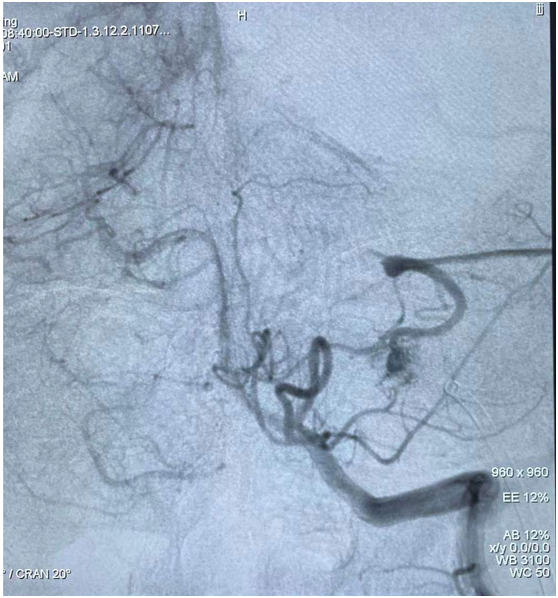

圖3:嘗試動脈途徑栓塞,栓塞劑返流嚴重

圖4:靜脈途徑導(dǎo)管到位良好